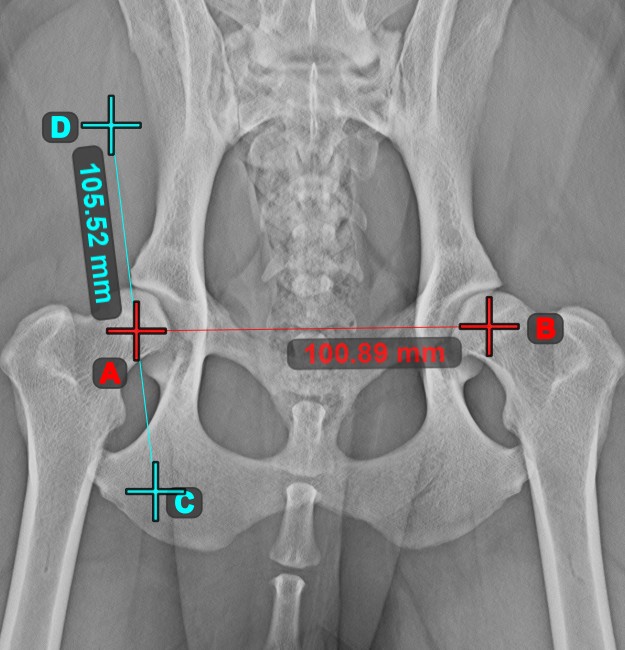

Angle of Lines¶

Select the tool from the left toolbar and assign it to one of the available mouse buttons. Start by selecting the first line from the ones already drawn on the scene, or place the start and end points to create the line. Follow the same steps for the second line of the measurement. The angle between the two lines will be automatically calculated.

Modify the start and end points of both lines by using the Select/Move Item tool. The angle between the two lines will be automatically recalculated.

If two lines do not intersect directly, the angle of their extended projections on the scene will be calculated.